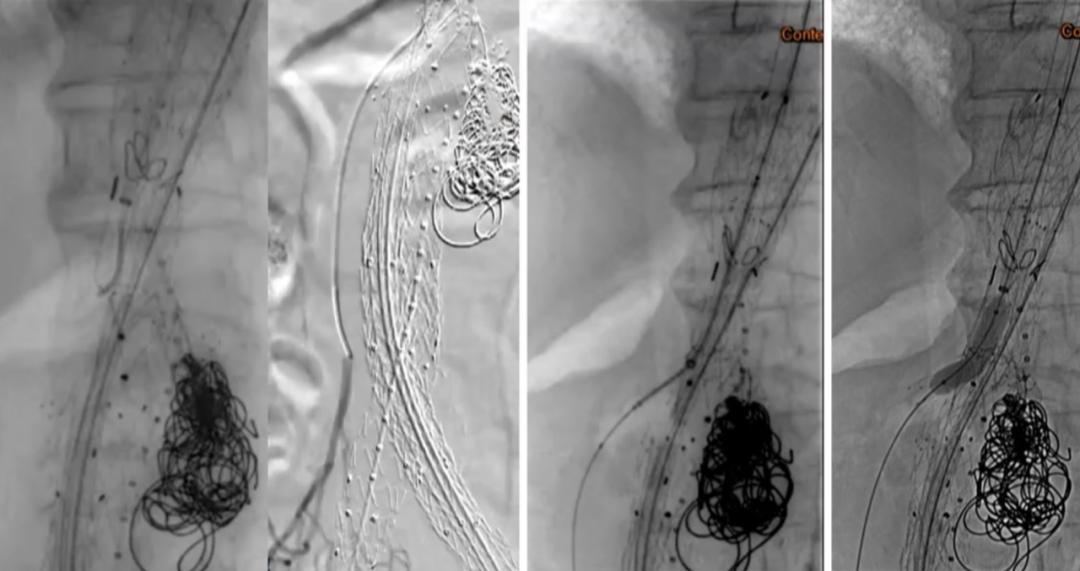

35-14-140mm分叉型支架,缝制内分支并固定,RRA、LRA:5mm Viabahn,CA、SMA:7mm Viabahn

分支预置导丝,回装支架

超选SMA,桥接8-100mm Viabahn,内衬8-60mm Absolute裸支架

超选CA,桥接8-100mm Viabahn

超选RRA烟囱支架,桥接6-100mm+6-50mm Viabahn

超选LRA烟囱支架,桥接6-100mm Viabahn

右侧:16-16-140mm Excluder髂腿;

左侧:16-16-120mm Excluder髂腿

术后造影